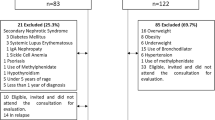

Study population

This cross-sectional observational study was conducted between February and May 2011. Thirty-seven patients aged between 7.9 and 18.8 years treated for SRNS with an estimated glomerular filtration rate (eGFR) of >90 ml/min/1.73 m2 [10] were recruited from the Pediatric Nephrology Divisions of Göztepe Research and Training Hospital and Cerrahpaşa Medical Faculty. SRNS was diagnosed according to the criteria recommended by the International Study for Kidney Disease in Children [11]. Based on renal biopsy results, the diagnoses of primary glomerular disease were as follows: focal segmental glomerulosclerosis (n = 30 patients), minimal change disease (n = 6), and diffuse mesangial proliferation (n = 1). The medical charts of each individual patient were reviewed for the following information: age, gender, age at diagnosis, disease duration, quantification of biochemical data, and the use of steroid, cyclosporine A, and other medications. The time-integrated mean values of serum concentrations of total protein, albumin, and lipids were calculated using the average of the values for the last 1 year. Hypoalbuminemia was defined by a serum albumin concentration of <2.5 g/dl. Nephrotic-range proteinuria was defined as >40 mg/m2 per hour of protein in a 24-h urine collection. All measurements of 24-h urinary protein excretions during relapses were documented and expressed as milligrams per square meter per day, and cumulative proteinuria was calculated as the area under the curve (AUC), which was computed by the trapezoidal rule using Microsoft Excel (Microsoft, Redwood, WA). All doses of prednisone and methylprednisolone were documented and converted to prednisolone equivalents. The mean daily doses of prednisolone and cyclosporine A (mg/kg per day) were calculated using the patient’s weight at the time of the use, and then their cumulative doses were also calculated as an AUC. Patients were not excluded if they were taking angiotensin-converting enzyme inhibitors (ACEIs), angiotensin receptor blockers (ARBs), or statins, since these treatments constitute best clinical practice.

Twenty-two healthy volunteers served as the control group. Control data were used to compare the results of cardiovascular measurements (aortic PWV, carotid IMT and LVH) and metabolic parameters. The study protocol was approved by the local Ethics Committee. An informed consent to participate in the study according to the recommendations of the Declaration of Helsinki on Biomedical Research Involving Human Studies was obtained from all children and/or their parents.

Thirty-seven consecutive patients (18 males, 19 females) with idiopathic SRNS and 22 healthy children were enrolled in the study. Clinical characteristics of the patients and the controls are summarized in Table 1. There were no differences in age, male to female ratio, or BMI-SDS between the patient and control groups. Seven of the patients were obese and only one was overweight. None of the patients were underweight.